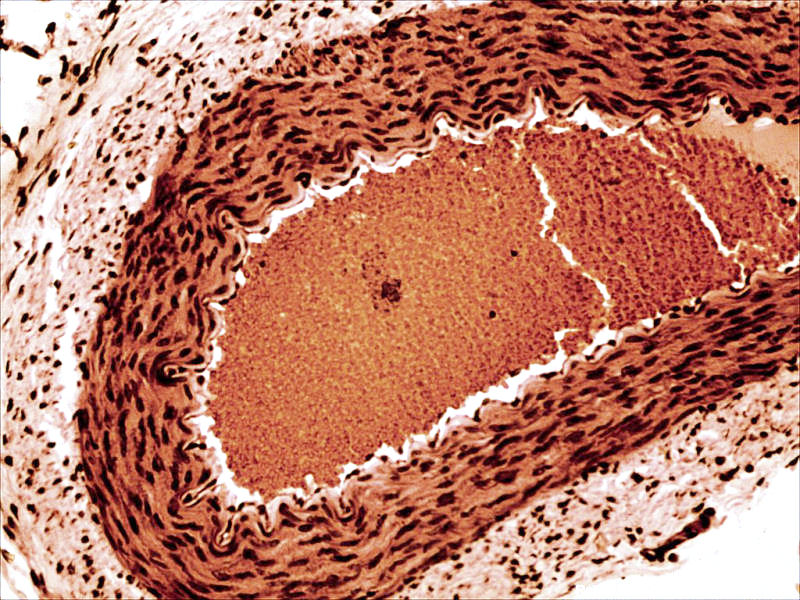

back Rabbit arteriole